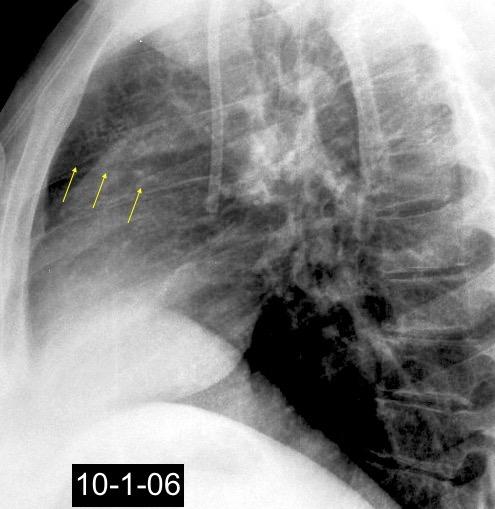

46. CALCIFICACIONES EN CÁSCARA DE HUEVO

Neumoconiosis

Gross GH et al. Egg-Shell calcification of lymph nodes. An update. AJR 1980

Silicosis (5%)

Neumoconiosis del carbón (1,3-6%)

Sarcoidosis. ( 5%)

Hongos y bacterias. Tuberculosis. Cocidioidomicosis

Histoplasmosis

Amiloidosis Idiopática

Silicosis

Grayson CE et al. Egg Shell calcification in silicosis. Radiology 1949

Silicosis secundaria al pulido con chorro de arena. Tejidos ”Denim”. (vaqueros, etc.)

Marchiori E et al. Conglomerated masses of silicosis in sandblasters: High-resolution CT findings. Eur Radiol 2006

Alper F,, et al. CT findings in silicosis due to denim sandblasting. Eur Radiol. 2008